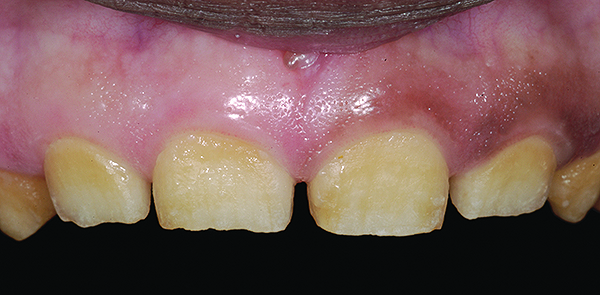

Figure 5. Preoperative 1:1 retracted frontal view.

Figure 5

The authors report on a 21-year-old patient who presented with severe discoloration and mild sensitivity of teeth (Figure 1). The teeth visible in his smile were very short, unsightly, and unbecoming for his age.

A thorough clinical examination and analysis were carried out to assess the esthetic and functional problems of the patient (Figure 2 through Figure 7). The medical history was non-contributory, except for mild leukoderma. Temporomandibular joint (TMJ) function was within normal range.